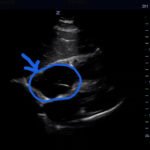

Bedside echocardiogram was performed, which revealed a free-floating thrombus in the right atrium on the sub-xiphoid view as seen in the video. The right atrium is denoted by the blue circle, in which a hyperechoic mobile mass can be seen. This finding was confirmed by an official echocardiogram which shows the thrombus in the right atrium extending through the tricuspid valve, as shown in the second image denoted by the red arrow. Significant right heart strain was also found, with severe pulmonary hypertension and intraventricular septal flattening.